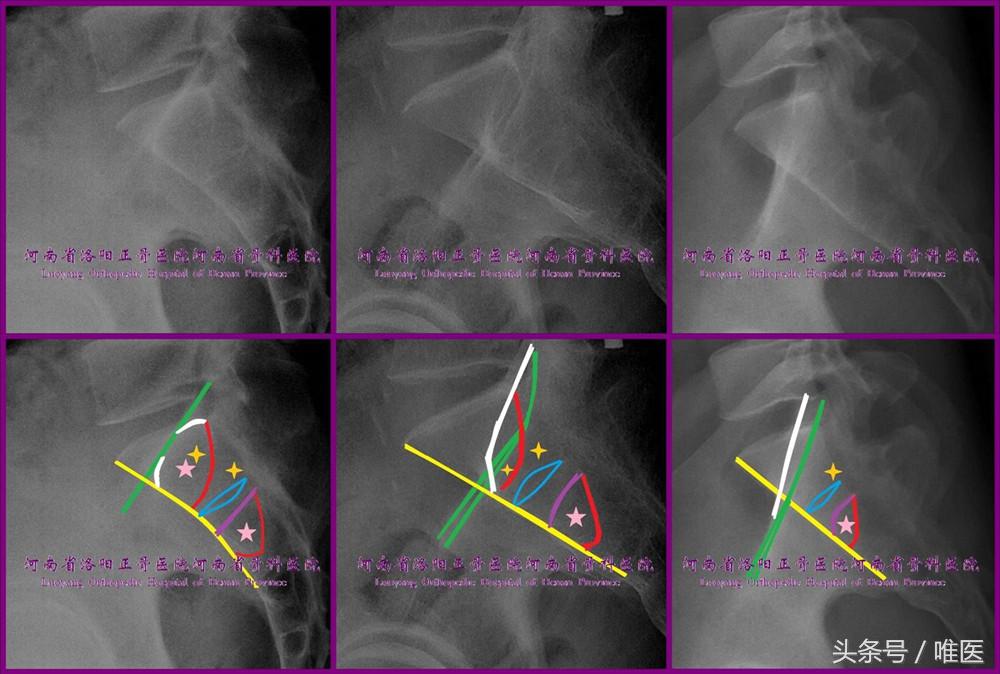

1. 标准骶骨侧位像(图4)

(1)方法:双侧ICD完全重叠,同时双侧坐骨大切迹(greater sciatic notch,GSN)完全重叠。

(2)内容:在标准骶骨侧位像上,除了Milton Lee Chip Routt, Jr.教授所发现的ICD[13]【为骶髂螺钉进钉点的确定提供了可靠的影像学标志(进钉点设在其尾后方),此后置钉的准确性显著提高、并发症发生率显著降低[13]】外,我们还可以获得其他同样有价值的信息。

其中最为重要的是骶神经根管前缘线。蔡鸿敏等最近发表了一篇文章专门对其进行了论述[18]:

①在第1、2骶段内骶神经根管始于同节段椎管的头端前缘的两侧,止于同节段骶前孔,其走形为由头端、后方、内侧至尾端、前方、外侧;

②在X线片上其密度低,尤其在标准骶骨侧位像上常仅其前缘线显像且多有中断现象而需要仔细辨识;

③建议在标准骶骨侧位像上辨识骶神经根管前缘线并以之作为骶髂螺钉安全通道的尾后界则可以避免内置物进入神经根管及骶管从而提高置钉的安全性。(图4、图5)

当然,在标准骶骨侧位像上,通过仔细阅读,我们还能看到SAS、骶椎体前缘线、骶1/2椎间盘(通常平分骶前孔),骶前孔上下缘等有价值的信息。

(3)意义:确定骶髂螺钉的“平向安全通道”及进钉点。骶1节段的“平向安全通道”如果存在,则其由ICD/SAS、骶神经根管前缘线、骶椎体前缘线三者围成(图4左列)。骶2节段的“平向安全通道”如存在,则由骶神经根管前缘线、骶椎体前缘线及经骶1骶前孔尾端的骶1椎体上终板平行线三者围成(图4)。平向骶髂螺钉的进钉点无疑需要定在“平向安全通道”内。但斜向骶髂螺钉的进钉点的选择却存在很大的自由度。宽泛地讲,ICD尾端及骶椎体前缘线后侧的很大的髂骨区域都可作为斜向进钉点的区域。然而,为了置钉手术的安全实施,我在此为大家推荐两种较为安全的进钉点的确定方法:

①经骶1骶前孔上缘作一条骶1上终板的平行线,该线与骶椎体后缘的交点即为最优的斜向进钉点[19];但因该进钉点位于骶神经根管前缘线的尾后侧,故术中缺乏螺钉未进入骶神经根管的证据;

②如标准骶骨侧位像上骶1节段存在平向通道,不论其空间足够置入平向螺钉与否,均可将斜向螺钉的进钉点确定于其内;这样做的好处在于其一开始即将螺钉进入骶神经根管的可能性予以排除(图4前列、中列)[11,18]。

图4. 标准骶骨侧位像。其可显示ICD(绿线)、骶神经根管前缘线(红线)、SAS(白线)、骶椎体前缘线(黄线)、骶1/2椎间盘(蓝线)、骶1骶前孔的上下缘(红线、紫线与黄线的交点)。五角星代表平向骶髂螺钉的进钉点,四角星代表斜向骶髂螺钉的进钉点。请对比上下图仔细阅读以便掌握。